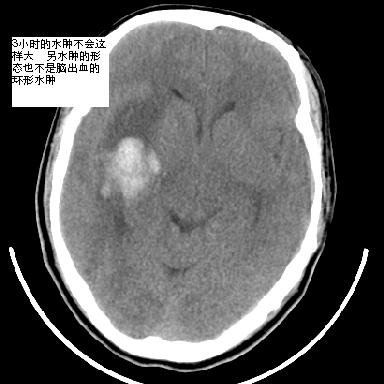

m 40突发头痛左侧偏瘫3小时

1是高血压性脑出血的好发部位,形态呈肾形,是高血压性脑出血的常见形状

另附部分资料:“血液溢出血管外形成血肿,其内含有大量血红蛋白、血浆白蛋白,球蛋白,因这些蛋白对x线的吸收系数高于脑质,故ct呈现高密度阴影,ct值达40~90h,最初高密度灶呈非均匀一致性,中心密度更高,新鲜出血灶边缘不清。基底节区血肿多为“肾”型,内侧凹陷,外侧膨隆,因外侧裂阻力较小,故向外凸,其它部位血肿多呈尖圆形或不规则形”